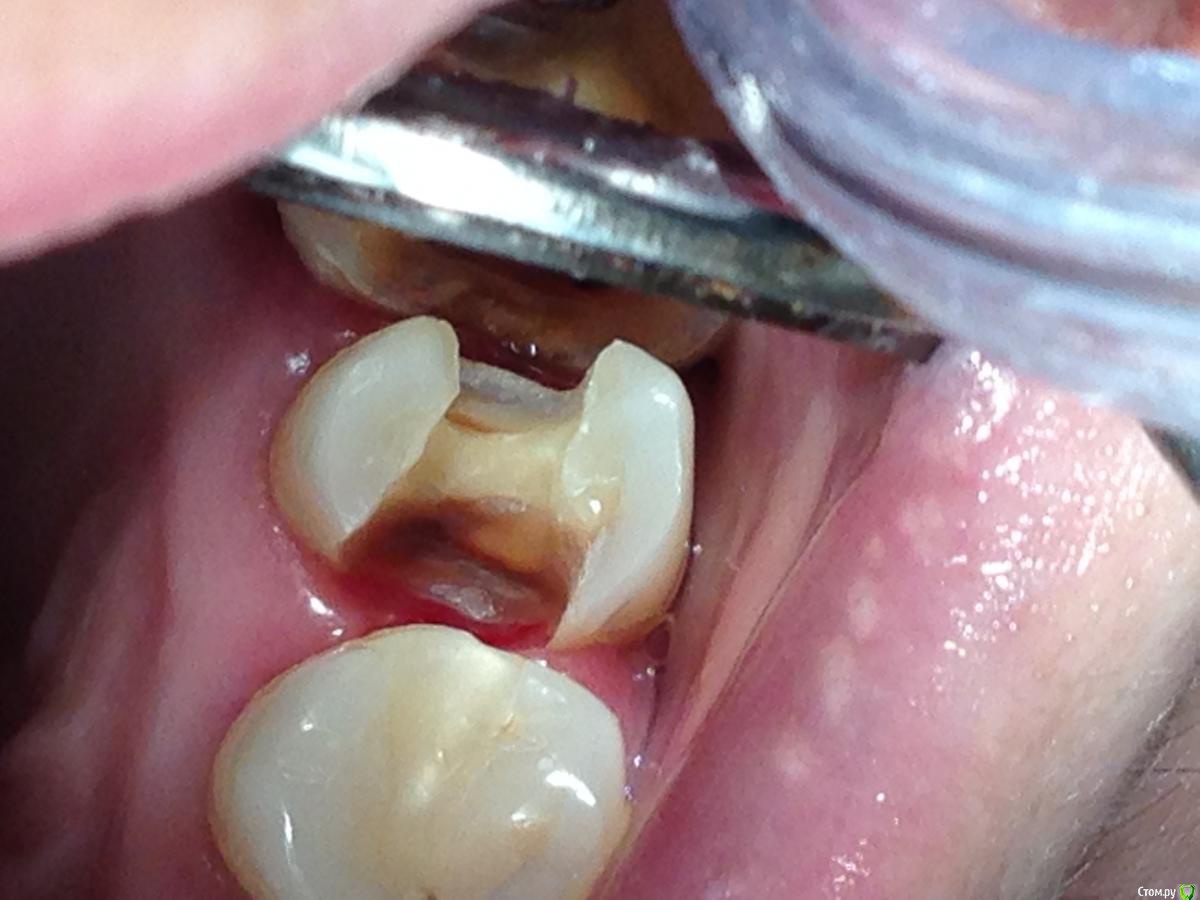

Salma Опубликовано 14 марта, 2016 Поделиться Опубликовано 14 марта, 2016 Зуб 15,не беспокоит,был под пломбой,пломбу сняли,небольшая некротомия.вопрос: что бы вы с ним далее делали? Фото не ахти, нотами плотно,кариесмаркером не красится. 1 Ссылка на комментарий

Петр Бриньковский Опубликовано 15 марта, 2016 Поделиться Опубликовано 15 марта, 2016 Зуб 15,не беспокоит,был под пломбой,пломбу сняли,небольшая некротомия.вопрос: что бы вы с ним далее делали? Фото не ахти, нотами плотно,кариесмаркером не красится. А разрушение апроксимально под десной? Плохо видно что-то, если да , то скорее всего лучше эндодонтию и коронку... иначе по переходу вкладки рано или поздно начнется разгерметизация и вторичный кариес Ссылка на комментарий